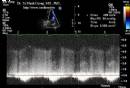

Nghiên cứu chức năng tâm trương thất trái và thất phải bằng siêu âm Doppler tim (Luận án Tiến sỹ Y học của TS. Tạ Mạnh Cường - Full text)